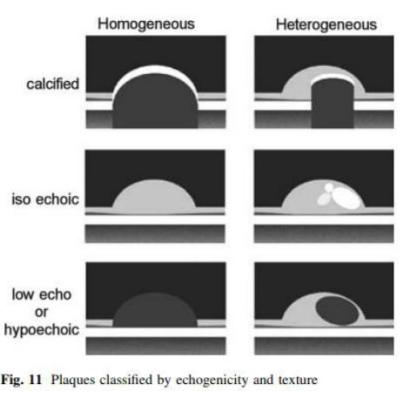

- * Plaque assessment 1) Plaque echogenicity, texture-homogeneous, heterogeneous-calcified, iso-echoic, hypo-echoic2) Doppler sonogra